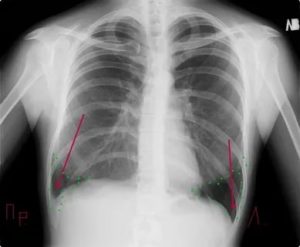

- состояние диафрагмы и лёгочно-диафрагмальных углов (синусов): оценивается симметричность стояния диафрагмы, угол синуса, его заполненность (наличие выпота при плеврите). Осумкованный экссудативный плеврит